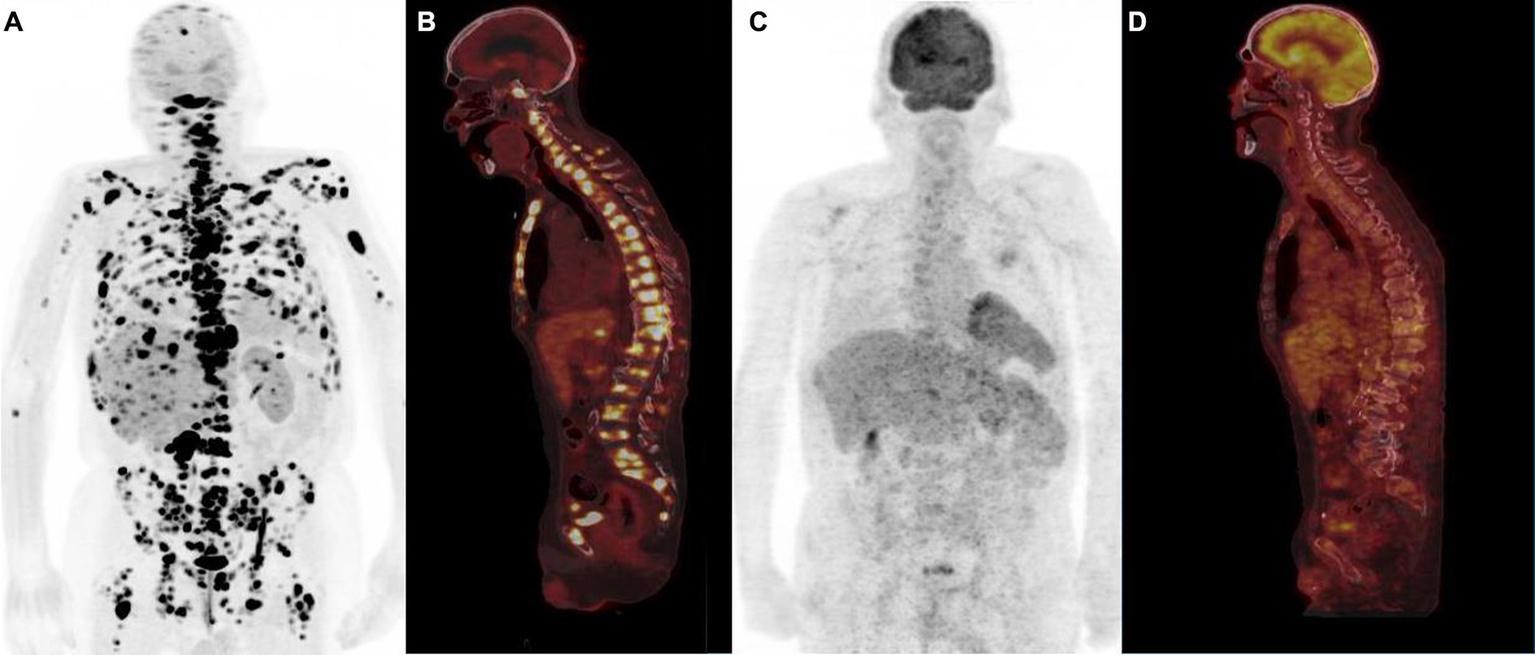

Figure 5

Typical example of “flip-flop” effect (anterior PET MIP, sagittal PET/CT) in a patient with metastatic low-grade (G1) small bowel NET. 18F-FDOPA PET showed multiple sclerotic bone metastases (A,B) not detectable by 18F-FDG PET (C,D), emphasizing the role of tumor grade in the selection of the optimal diagnostic radiotracer.